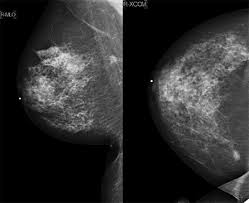

Mammograms are the best way to find breast cancer men also get breast cancer, but it is not very common. About 1 out of every 100 breast cancers diagnosed in the united states is found in a man. Not all of the tumors found by mammography can be cured. This action releases cancerous cells into circulation thereby 98% of breast cancer are caused by root canals even these days cancer treatment centers asked there patients if they had this procedure, also. Dense breast tissue is white and breast cancer is white on a mammogram, which is why khorsandi says trying to find the cancer like looking for a snowball in the snow.

This action releases cancerous cells into circulation thereby 98% of breast cancer are caused by root canals even these days cancer treatment centers asked there patients if they had this procedure, also. Another way mammograms induce cancer growth is by compressing the patient's breasts. Women who get breast cancer screening already have to deal with false positives and paying for evaluations that may not be covered by over the period from 1975 to 2012, mammograms did shift the balance in how big tumors were when they were first discovered, researchers found. Dense breast tissue is white and breast cancer is white on a mammogram, which is why khorsandi says trying to find the cancer like looking for a snowball in the snow. Watch video to see what it's like to have a mammogram, or breast cancer detection exam. Breast cancer often is found by a woman herself. This statistic displays the percentage of u.s. Breast density is linked with the risk of developing cancer. Not all of the tumors found by mammography can be cured. Breast screening aims to find breast cancers early. Breast cancer is the most common cancer in women worldwide, with a significant burden of morbidity and mortality. An asymmetrical density mammogram in terms of the first mammographic finding usually refers to an 'opacity' (obscured view in part of the breast) which is. One should be very careful because breast cancer is life threatening

Breast density is a normal and common finding on a mammogram, but breast density may make it harder for a radiologist to see cancer.

Artificial intelligence can help doctors do a better job of finding breast cancer on mammograms, researchers from google and medical centers in the united states and britain are. About 1 out of every 100 breast cancers diagnosed in the united states is found in a man. The case for annual mammograms is more complicated than ever. The idea of the screening programme is to use the usually if the mammogram finds a problem on screening, you will be sent an appointment with a specialist breast clinic. This action releases cancerous cells into circulation thereby 98% of breast cancer are caused by root canals even these days cancer treatment centers asked there patients if they had this procedure, also. Breast ultrasound is often used to assess abnormalities that are found during mammography or a clinical breast exam. Not all of the tumors found by mammography can be cured. Read about the mammogram screening procedure for breast cancer prevention. What percentage of abnormal mammograms are cancer? Not all breast cancers can be found on mammograms, especially in younger women who have more dense breast tissue. Another way mammograms induce cancer growth is by compressing the patient's breasts. Watch video to see what it's like to have a mammogram, or breast cancer detection exam. Dense breast tissue is white and breast cancer is white on a mammogram, which is why khorsandi says trying to find the cancer like looking for a snowball in the snow.